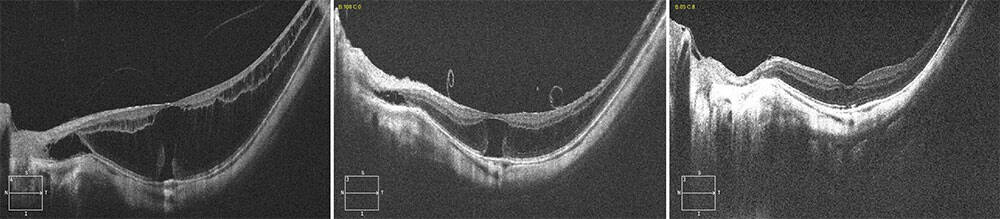

Figure 1. Classification de Govetto. Celle-ci repose sur la contraction des couches rétiniennes observées sur le B-scan de l’examen en tomographie en cohérence optique.

A et B. Stade 1. MEM avec préservation de la dépression fovéolaire. Elle est visible à la surface de la rétine sur le B-scan (A). Il y a des plis rétiniens superficiels. On retrouve le creux de la dépression fovéolaire sur le mapping (B). C et D. Stade 2. Disparition de la dépression fovéolaire sans couche rétinienne interne ectopique (EIFL, Ectopic Inner Foveal Layer). On observe un aspect « d’inversion de l’entonnoir fovéolaire » sur le B-scan (C). Le creux de la dépression fovéolaire n’est plus visible sur le mapping (D).

E et F. Stade 3. Disparition de la dépression fovéolaire (EIFL), couches rétiniennes internes encore bien définies. La rétraction est telle que l’espace de la dépression fovéolaire est occupé par les couches rétiniennes internes (E). Il est néanmoins toujours possible de les distinguer. L’épaisseur maculaire est augmentée (F). G et H. Stade 4. Disparition de la dépression fovéolair (EIFL), désorganisation des couches rétiniennes internes. On observe des plis rétiniens intéressant l’ensemble des couches internes (G). L’épaisseur maculaire est augmentée (F).